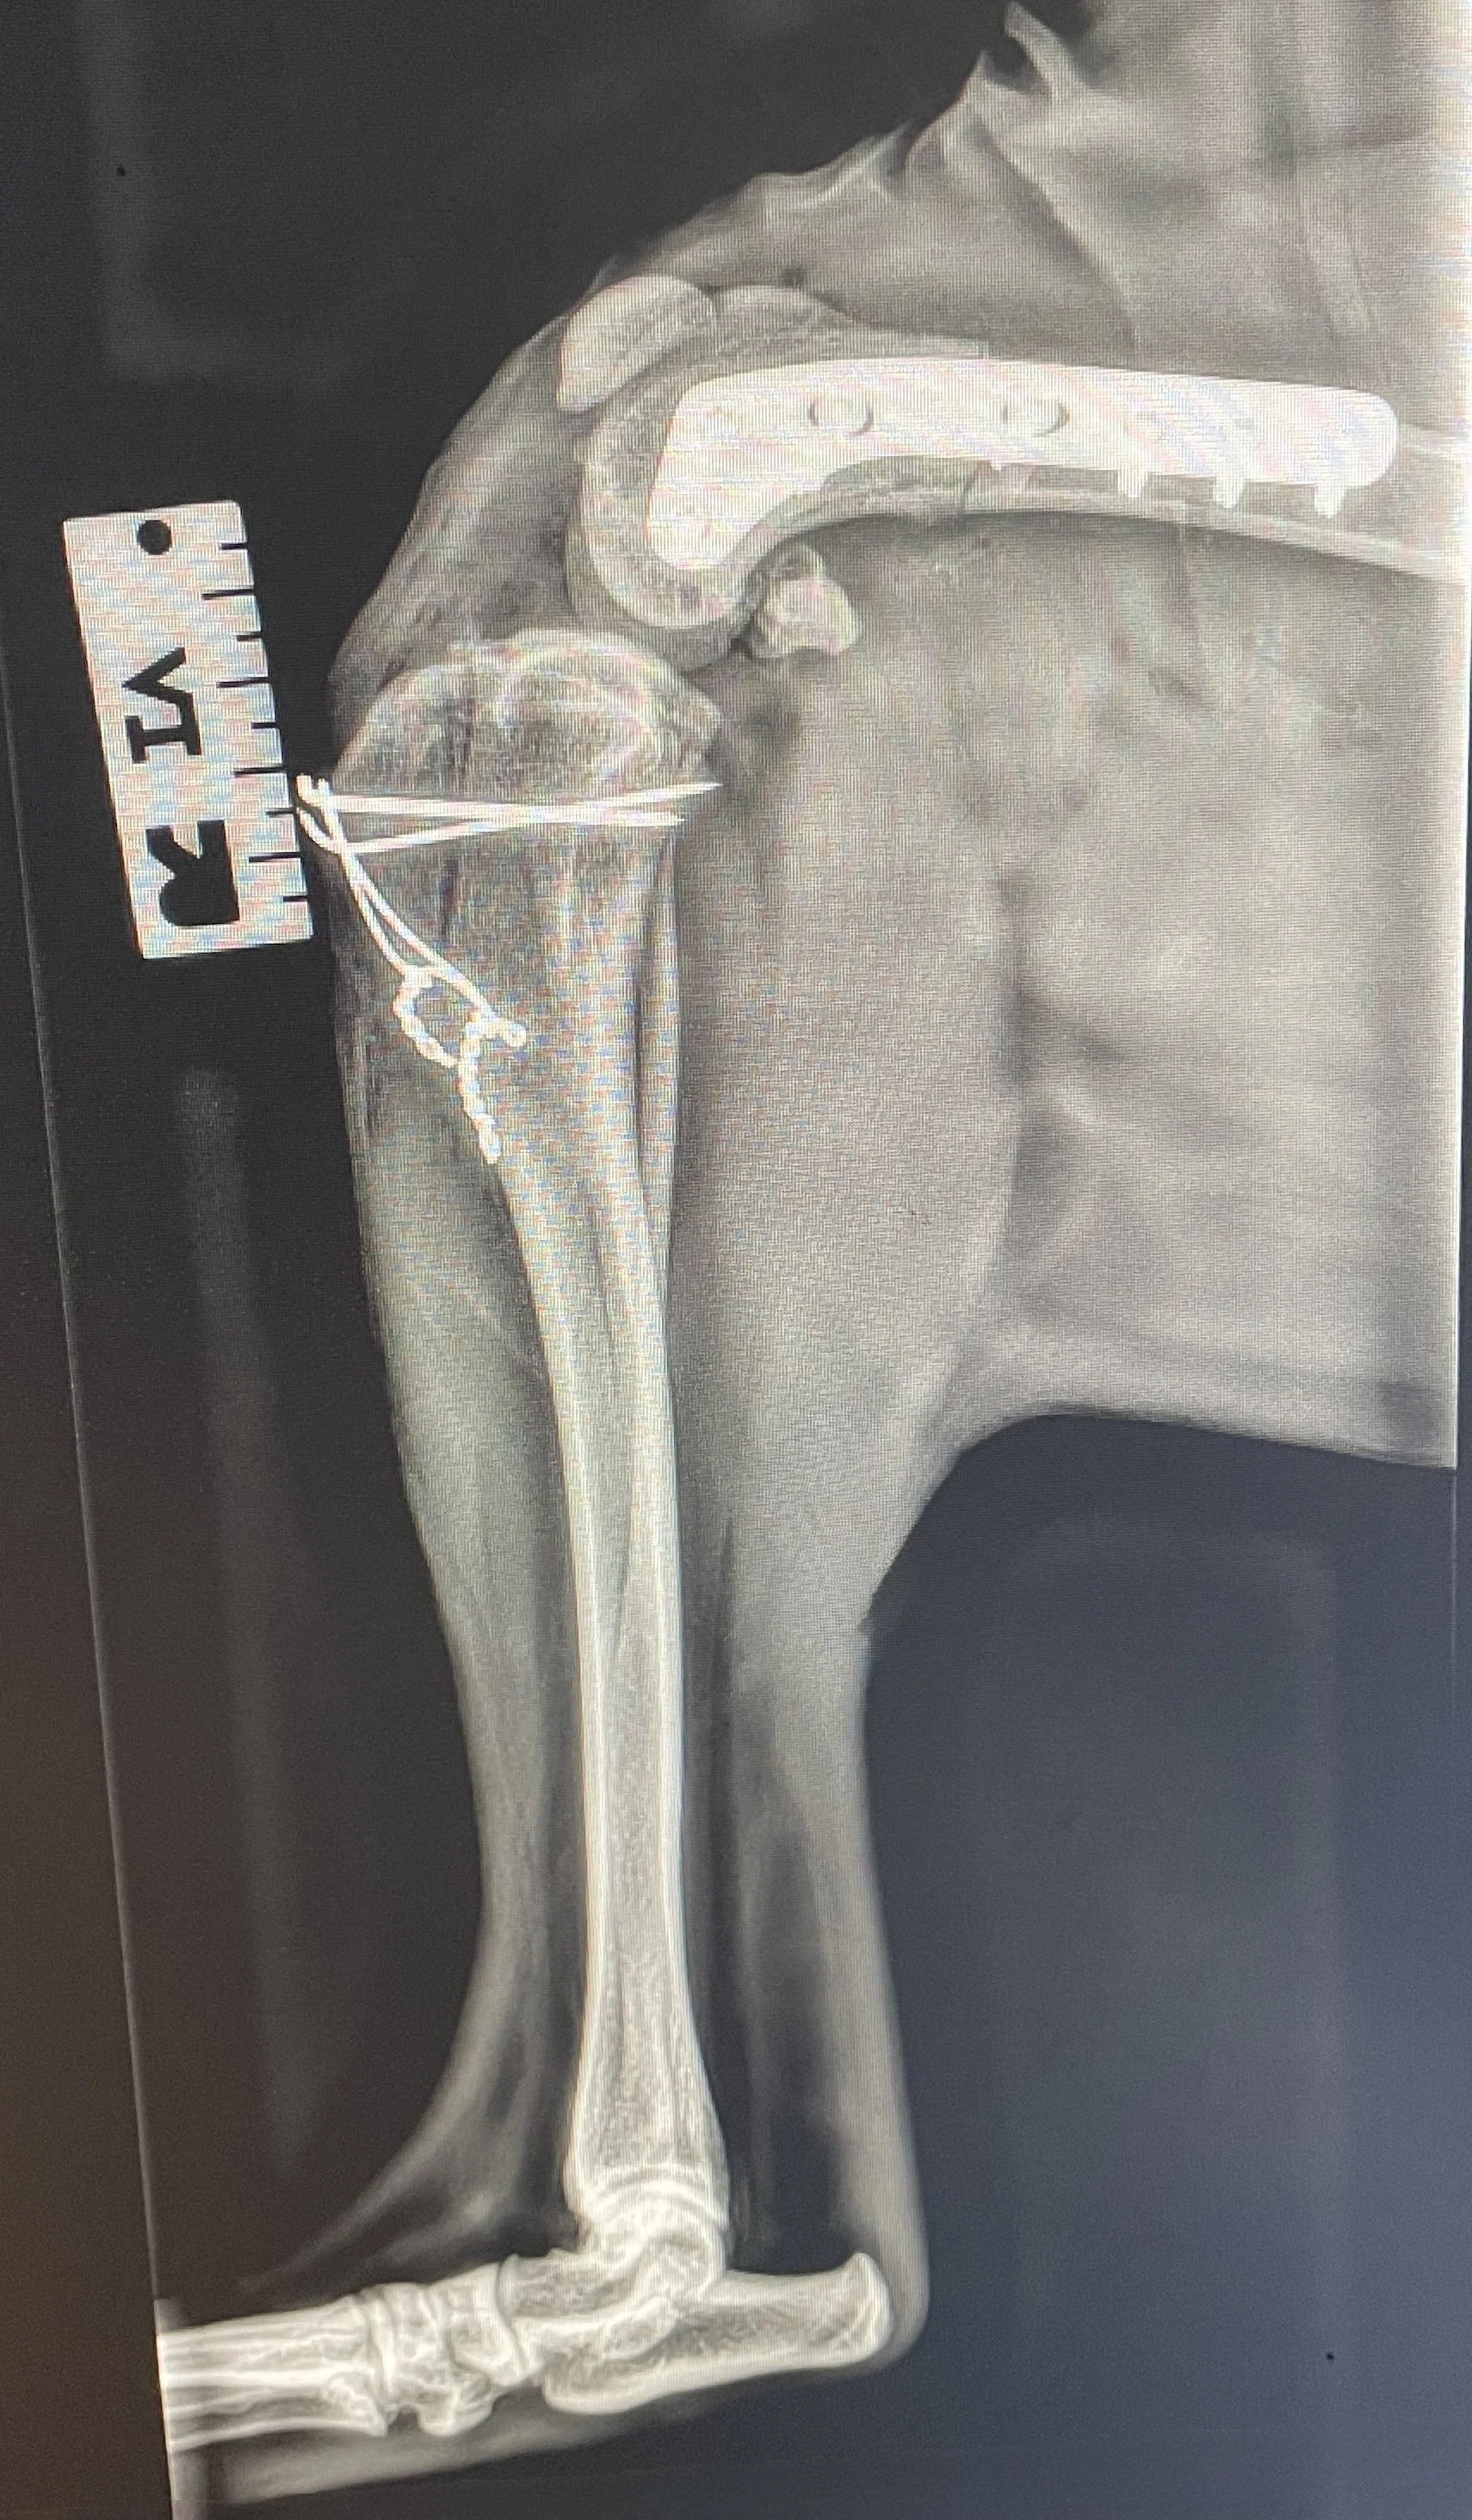

Distal Femoral Osteotomy is a corrective bone surgery in which a precise cut is made in the distal femur (near the knee), and the bone is realigned to correct:

Once corrected, the bone is stabilized with a bone plate and screws. This realignment allows the patella to track correctly within the trochlear groove, resolving the underlying biomechanical cause of luxation.

• Regular rechecks and X-rays to monitor bone healing

Post-operative radiograph of a DFO performed by Dr Davids.